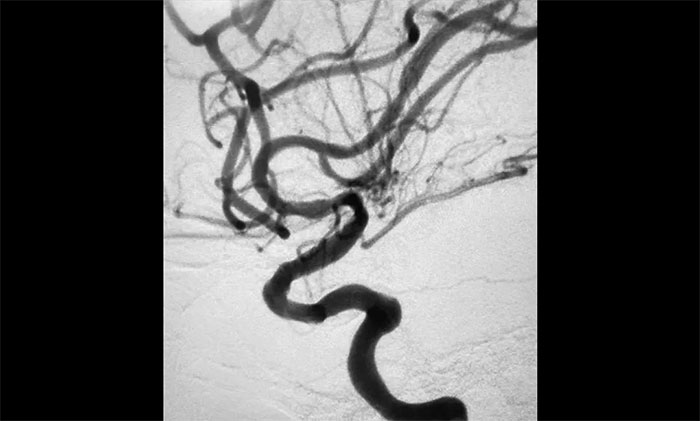

▲术后DSA影像:左侧颈内动脉血流恢复

术中脑血管造影可见:左侧颈内动脉眼动脉段以远闭塞……余血管未见明显异常。张琪博士在刘春、周林华、李喆医生协助下,通过右侧股动脉穿刺,将微导管、微导丝送达左侧大脑中动脉M1段,经多次抽吸+支架拉栓,顺利取出血栓。造影显示,颈内动脉眼动脉段血流恢复。

随后,微导丝超选至左侧大脑中动脉M1段远端,并以多枚球囊扩张残余重度狭窄处,造影提示狭窄较前明显改善,远端血流改善明显。最后顺利放入支架,造影提示支架贴壁良好,支架内血流通畅,远端血流良好,手术顺利完成。